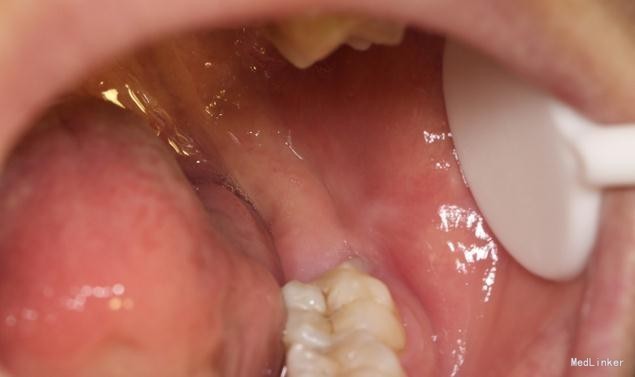

随访 讨论

效果很好,患者满意